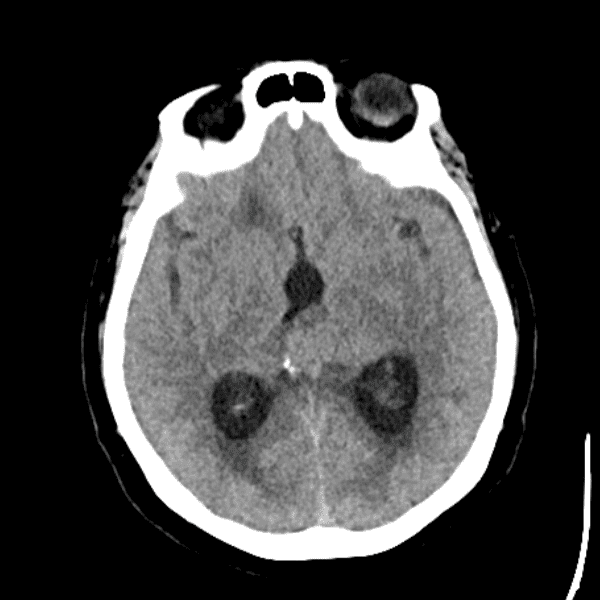

Classic Cases